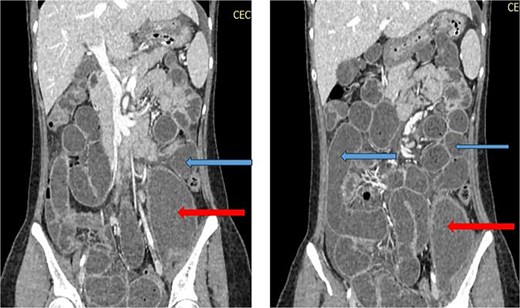

She was treated conservatively with IV fluids, analgesics, and antibiotics. Ultrasound-guided catheter drainage of the abscess yielded ~100 ml of pus. A post-procedure X-ray confirmed the position of the drainage catheter (Fig. 4). Anti-tuberculous therapy (ATT) was initiated under the DOTS strategy. Her obstruction resolved, and she was discharged on Day 4 with advice to continue ATT as per DOTS, a high-protein diet and follow-up in the surgery outpatient department. Orthopaedics consultation advised lumbar corset for ambulation support.

X-ray abdomen showing pig tail catheter in left inguinal region and nasogastric tube in stomach (anteroposterior and lateral).